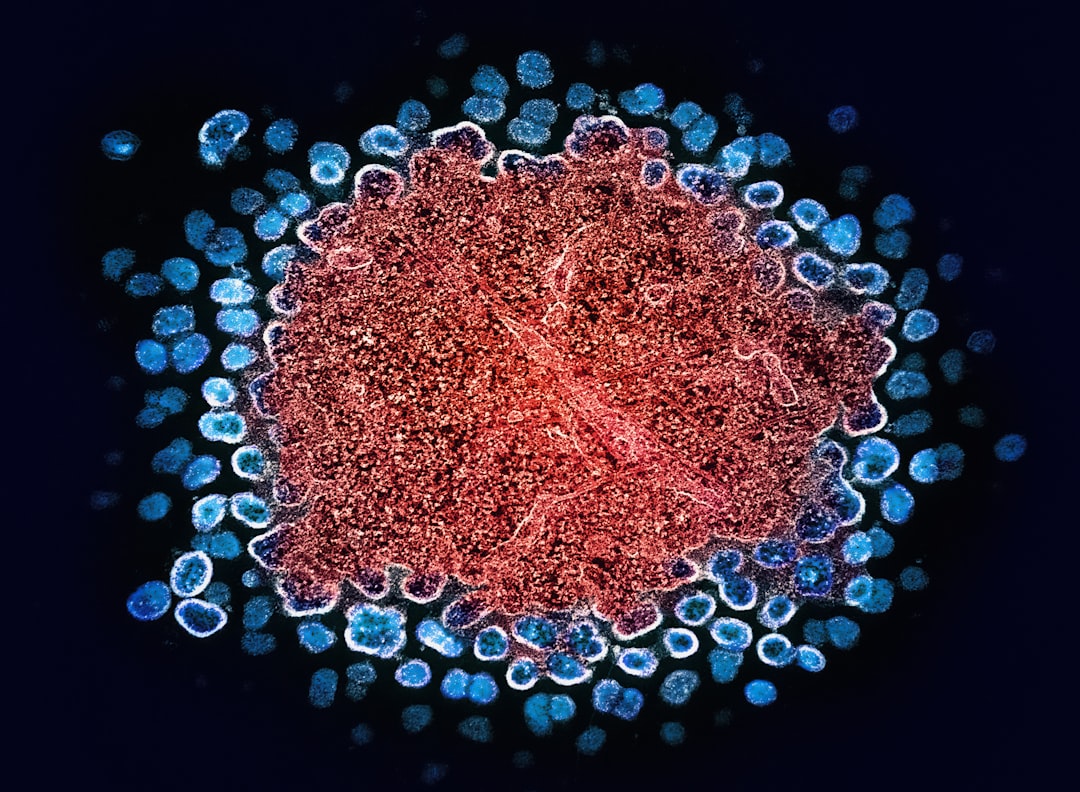

nk세포치료 일본, 암치료의 새로운 패러다임은?

nk세포치료란 무엇인가?nk세포치료 일본에서 주목받고 있는 이유는 결국 이 치료법이 우리의 몸에서 자연스럽게 암세포를 공격하는 능력을 활용하기 때문입니다. NK세포, 즉 자연살해세포는 면

NK세포 치료 보험, 암환자를 위한 혜택은?

NK세포 치료 보험의 기초 이해하기NK세포 치료는 면역세포를 이용하여 암세포를 공격하는 혁신적인 방식의 치료법입니다. 이 치료는 자연 킬러(Natural Killer) 세포를 이용하여 인체의 면역력을 강